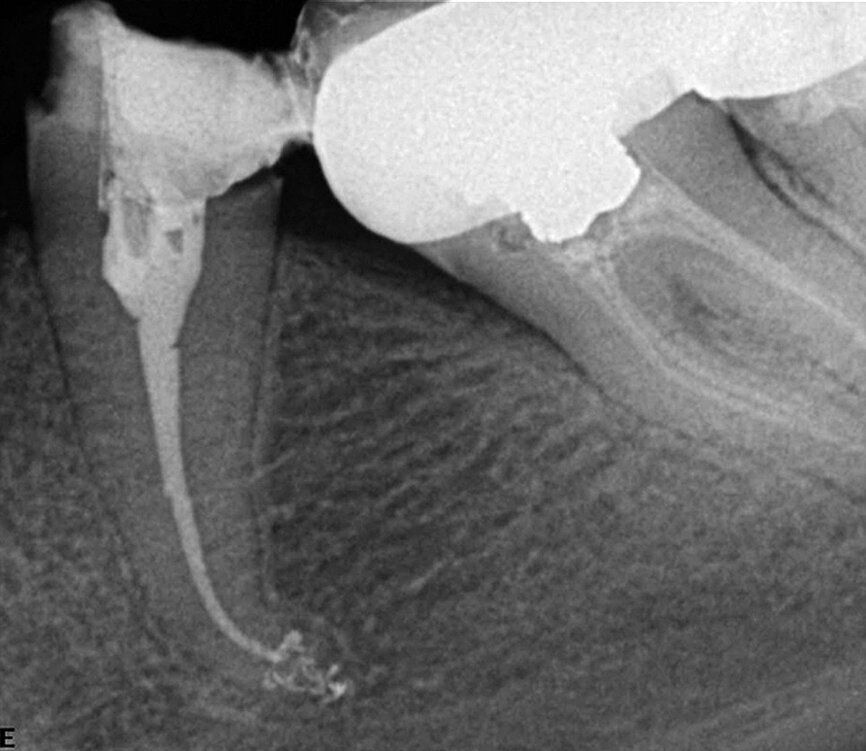

Fig. 5: The case was referred for retreatment due to the failure of the previous root canal therapy. Following the shaping (TF-adaptive) and cleaning (Sleiman protocol), and upon the challenging but successful search for the distal canal, a 3-D obturation was performed, which allows showing the isthmus between the mesial and distal canals as well as a very coronally located lateral canal in the palatal root.